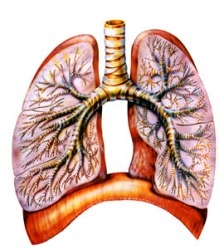

Представляет собой заболевание, поражающее серозную оболочку лёгкого (плевру). Причиной возникновения этого заболевания является инфекционное поражение легких. Туберкулёзный плеврит может возникать как самостоятельное заболевание, а может развиться на фоне других форм туберкулёза.